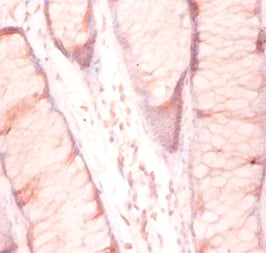

IHC (Immunohiostchemistry)

(Immunohistochemistry of paraffin-embedded human pancreatic tissue using AAA118129 at dilution of 1:100)